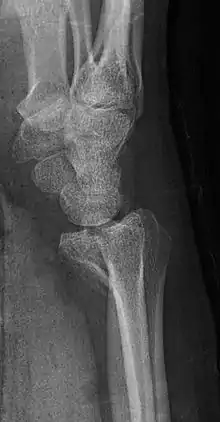

| Barton's fracture | |

A Barton's fracture is a type of wrist injury where there is a broken bone associated with a dislocated bone in the wrist, typically occurring after falling on top of a bent wrist.[1] It is an intra-articular fracture of the distal radius with dislocation of the radiocarpal joint.[2]

There exist two types of Barton's fracture – dorsal[3] and palmar, the latter being more common. The Barton's fracture is caused by a fall on an extended and pronated wrist increasing carpal compression force on the dorsal rim. Intra-articular component distinguishes this fracture from a Smith's or a Colles' fracture. Treatment of this fracture is usually done by open reduction and internal fixation with a plate and screws, but occasionally the fracture can be treated conservatively.[4]